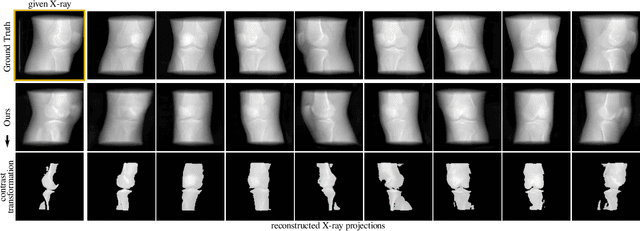

Abstract:Computed tomography (CT) is an effective medical imaging modality, widely used in the field of clinical medicine for the diagnosis of various pathologies. Advances in Multidetector CT imaging technology have enabled additional functionalities, including generation of thin slice multiplanar cross-sectional body imaging and 3D reconstructions. However, this involves patients being exposed to a considerable dose of ionising radiation. Excessive ionising radiation can lead to deterministic and harmful effects on the body. This paper proposes a Deep Learning model that learns to reconstruct CT projections from a few or even a single-view X-ray. This is based on a novel architecture that builds from neural radiance fields, which learns a continuous representation of CT scans by disentangling the shape and volumetric depth of surface and internal anatomical structures from 2D images. Our model is trained on chest and knee datasets, and we demonstrate qualitative and quantitative high-fidelity renderings and compare our approach to other recent radiance field-based methods. Our code and link to our datasets will be available at our GitHub.